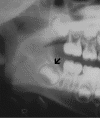

Radiology of the case:

Panoramic radiography shows a radiolucent, multilocular mass that expanded the left ramus (A). It involves the ramus tooth #17 to #21 and also extends into the left condyle. The margin of the lesion is scalloped and non-sclerotic. No periosteal reaction is present. Some fine trabeculae are present but no radiodensity suggestive of mineralized content are present.